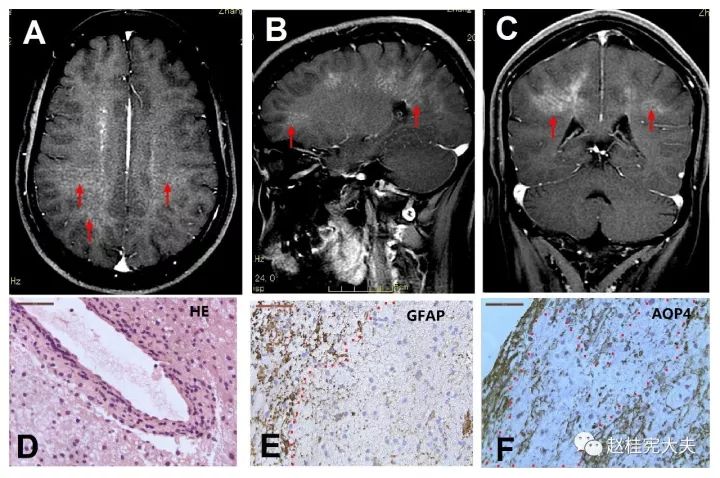

自身免疫胶质纤维酸性蛋白(gfap)星形细胞病_澎湃号·湃客_澎湃新闻